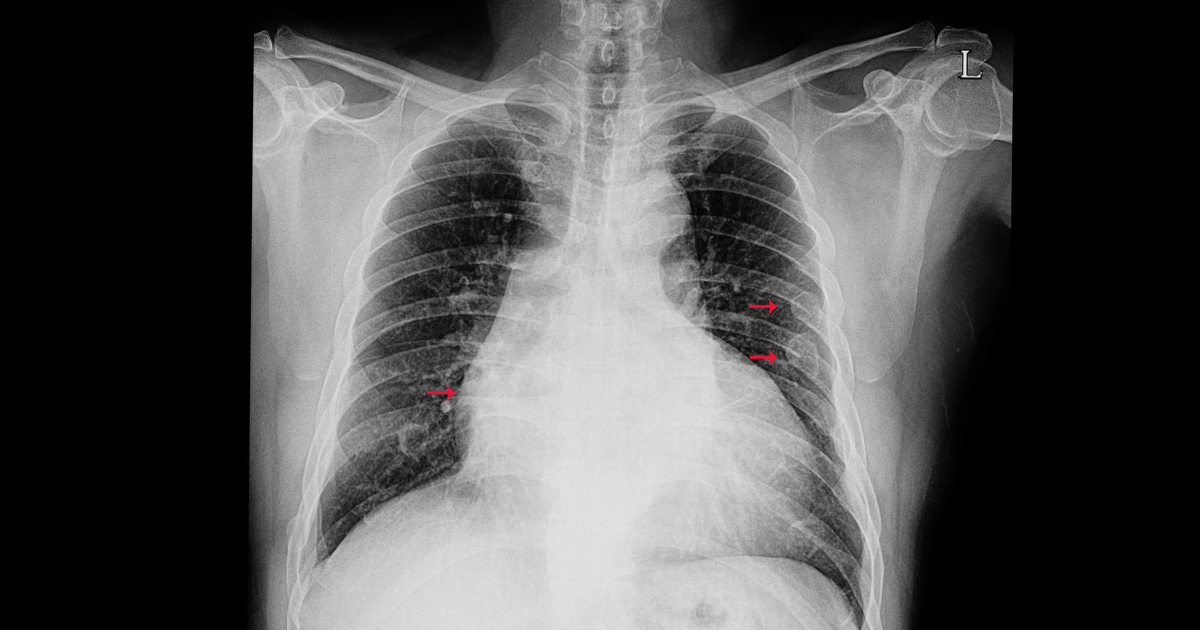

How to diagnose broken ribs. The doctor will first give you an exam to look. If you have a broken rib, symptoms such as bruising, pain and swelling are considered very Press on the injured area.

A broken rib typically causes sharp pain. To diagnose a rib injury, it’s best to see a medical professional who can look at your injuries with professional tools and technology. You may also feel or hear a crack or pop when the.

Sometimes, you may be able to feel a break in your rib by rubbing your finger over the rib. If you have a tender area on your ribs that hurts with every breath, you may have a broken rib. If you heard cracking during the injury or you hear or feel cracking when you move or.